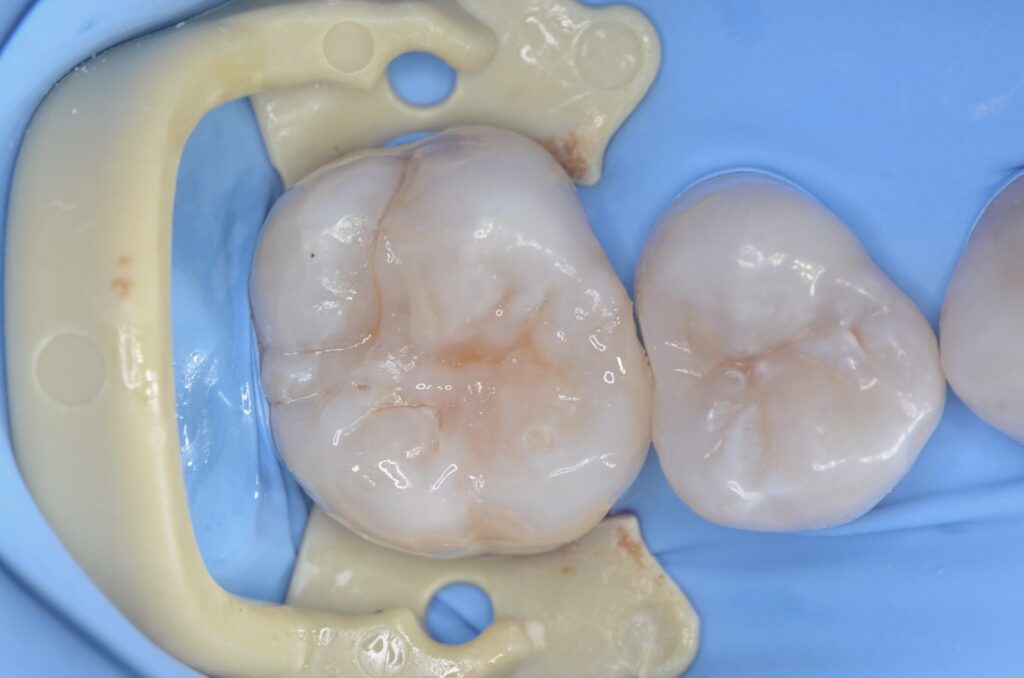

虫歯の治療・ダイレクトボンディング

80代 虫歯治療 ダイレクトボンディング #32

Before

After

| 年齢 | 80代 | 治療方法 | ダイレクトボンディング |

|---|---|---|---|

| 性別 | 女性 | 通院回数 | 2回 |

| 主訴 | むし歯を治したい 。歯を長持ちさせたい | 費用 | 115,500円(税込) |

| 治療のメリット | 歯を削る量を少なくできる・自然な見た目・境目がピッタリできる | ||

| 治療のデメリット | 大きい虫歯治療には適応できない場合がある | ||